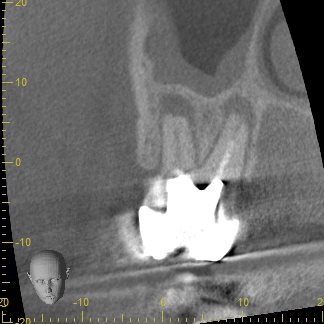

歯根周囲の骨の吸収が大きく、保存が可能かどうか判断が難しいと思われたCT画像

従来のレントゲン画像は全てのものが影絵として一枚の平面に写し出されるため、根の先の病巣の大きさを詳しく調べることが困難です。そこで、CT撮影を行うことで、3次元的に様々な角度で確認し、根の先の病巣がどれほどの大きさを調べその歯が保存可能なのかどうかを診ていきます。

この写真は術前のCT画像です。

歯根の周囲に見られる黒くなっている部分は、細菌の感染により骨が吸収しています。根尖病巣と呼ばれるこの部分が大きいほど治る確率が下がると言われ、根管内の細菌数も多いことがほとんどです。

ここまでの吸収があると、歯根が破折してる可能性を考える必要があります。